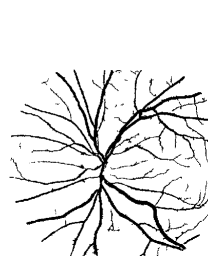

Retinal blood vessels generally show a coarse to fine centrifugal distribution and appear as a wire mesh-like structure or tree-like structure. Their morphological features, such as length, width and branching, play an important role in diagnosis, screening, early detection and treatment of various cardiovascular and ophthalmologic diseases such as stroke, vein occlusions, diabetes and arteriosclerosis [1]. The analysis of morphological features of retinal blood vessels can facilitate a timely detection and treatment of a disease when it is still in its early stage. Moreover, the analysis of retinal blood vessels can assist in evaluation of retinal image registration [2], the relationship between vessel tortuosity and hypertensive retinopathy [3], retinopathy of prematurity [4], arteriolar narrowing [5], mosaic synthesis [6], biometric identification [7], foveal avascular region detection [8] and computer-assisted laser surgery [1]. Since cardiovascular and ophthalmologic diseases have a serious impact on human’s life, the analysis of retinal blood vessels becomes more and more important. It is of great significance in many clinical applications to reveal important information of systemic diseases and support diagnosis and treatment. As a result, the requirement of vessel analysis system grows rapidly in which the segmentation of retinal blood vessels is the first and one of the most crucial steps.